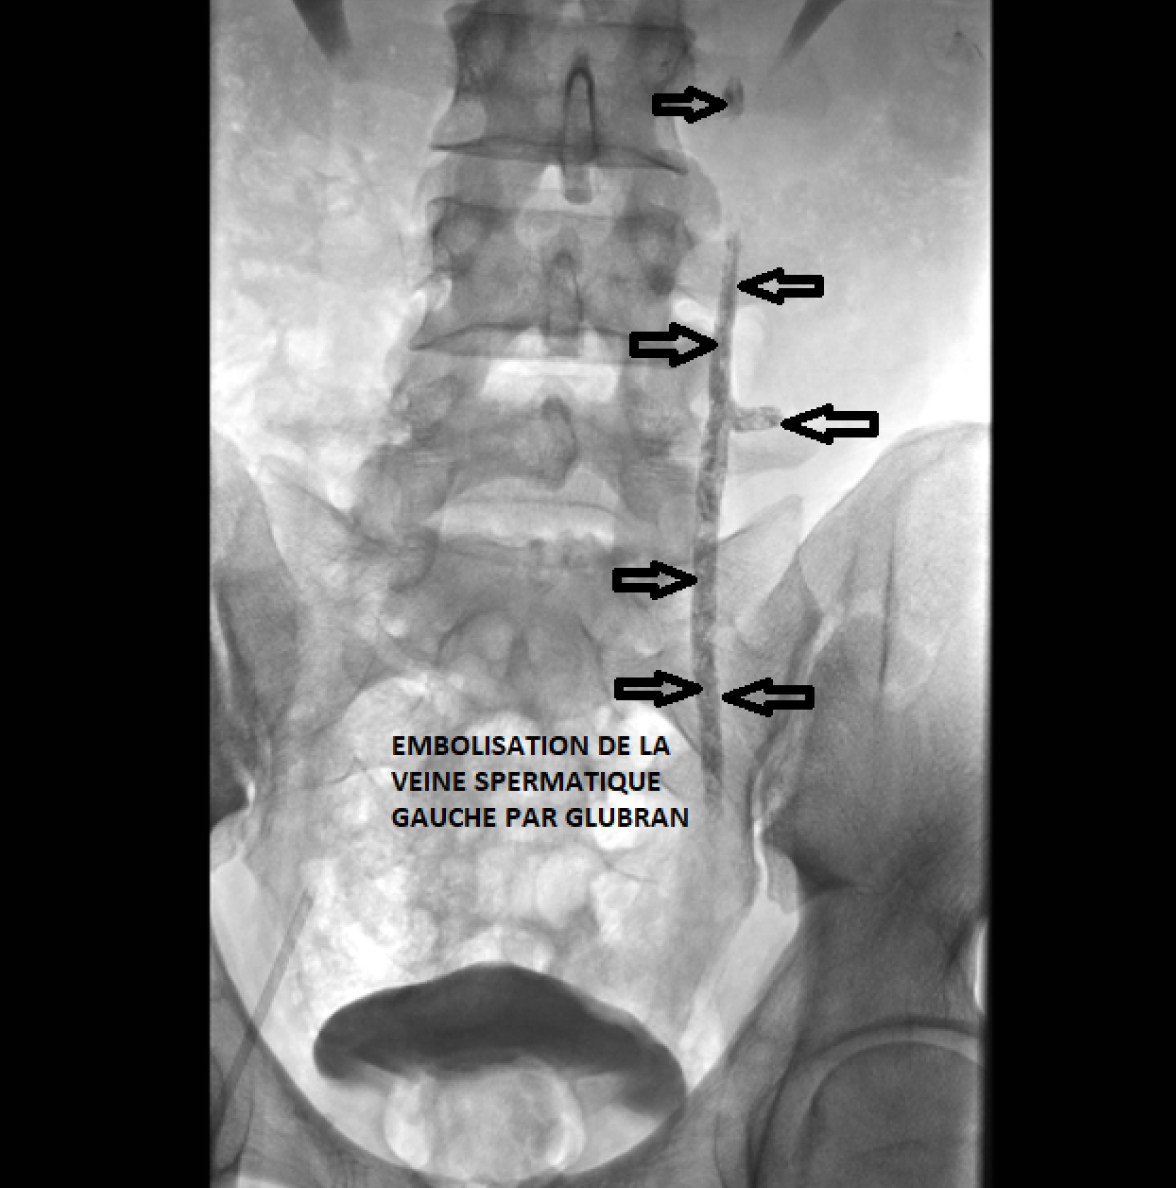

La veine testiculaire gauche est la plus souvent responsable de la varicocèle. Après avoir objectivé sa dilatation et son incontinence par l’injection de produit de contraste iodé , elle est embolisée par un agent liquide (colle biocompatible). La navigation radiologique en temps réel (scopie) est de mise tout au long du traitement. Vous êtes en décubitus dorsal sur la table d’opération, et vous pouvez assister à votre intervention sur écran si vous le souhaitez.